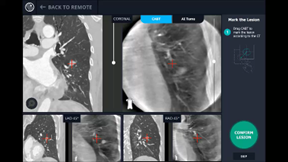

Sammenlignet med konventionel fluoroskopi kan højopløselig 3D-billeddannende CT-konstruktion i forbindelse med en bronkoskopi give real time CT-billeder, således at bronkoskopet eller biopsiværktøjer kan guides direkte til læsionen, som kan biopteres under direkte vejledning af CT.

I de senere år har CBCT med integreret augmented fluoroskopi vist sig at være en lovende billeddiagnostisk modalitet til lokalisation og bioptering af perifere lungelæsioner ved bronkoskopi. CBCT kan både benyttes i kombination med navigationsbaserede robotsystemer eller som ”stand alone” system sammen med det konventionelle bronkoskop (herunder de ultratynde bronkoskoper). CBCT tillader 3-dimensionel billeddannelse og mulighed for segmentation af luftvejene ud til infiltratet i planlægningsfasen, real time augmented fluoroskopi under selve proceduren samt bekræftelse af placering af skop og biopsiværktøjer i læsionen i forbindelse med biopteringen (tool in lesion).

Billede 3: CBCT med augmented fluoroskopi